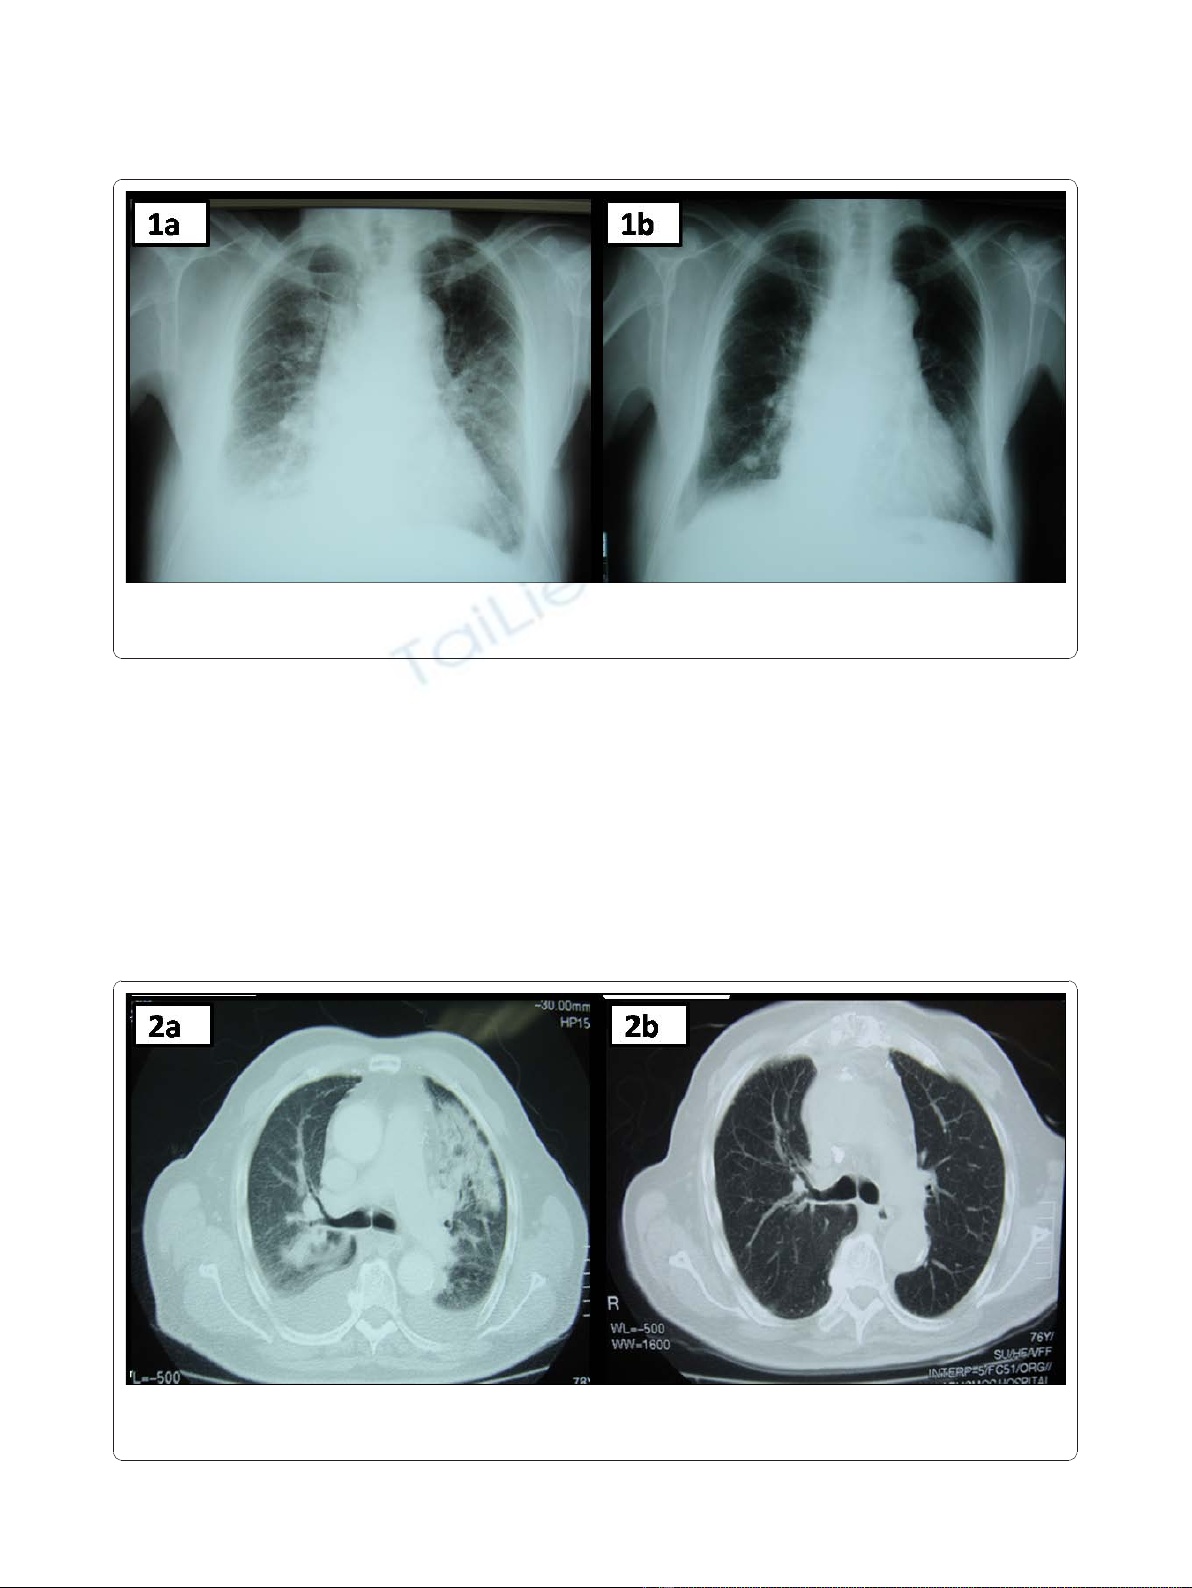

(CRP) 1.0 mg/dL (normal range <0.5 mg/dL). A chest

radiogram showed bilateral perihilar alveolar edema

with a “butterfly”appearance and bilateral pleural effu-

sions (Figure 1a). A transesophageal, two-dimensional

Following emergent treatment of CHF, all symptoms

and physical signs were completely resolved. Addition-

ally, a new chest radiogram showed significant improve-

ment of the aforementioned radiographic findings

(Figure 1b). Six sets of blood cultures from three sepa-

Figure 1 Chest Radiograms. a. Chest X-ray demonstrating bilateral perihilar alveolar edema with a “butterfly”appearance and bilateral pleural

effusions. b. Chest X-ray after pharmaceutical treatment for the congestive heart failure symptoms. Most of the initially appeared radiographic

findings have been almost completely resolved.